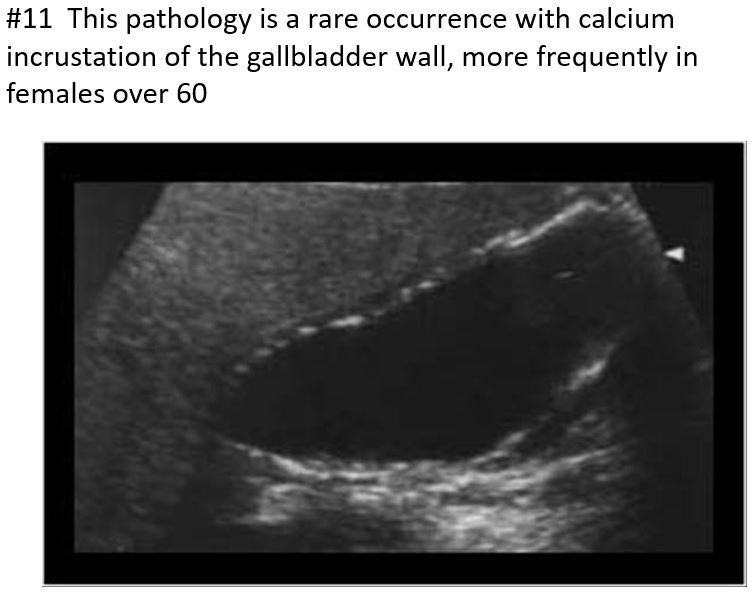

Rare occurrence - calcium incrustation of the gallbladder wall.

often in older female patients over 60

Associated with gallstones, a form of chronic cholecystitis

Significance: 25% of these patients will develop cancer on the gallbladder wall.

Bright echogenic echo is seen in the region of the gallbladder with posterior shadowing.

The differential will include a packed bag or WES sign.

Porcelain Gallbladder